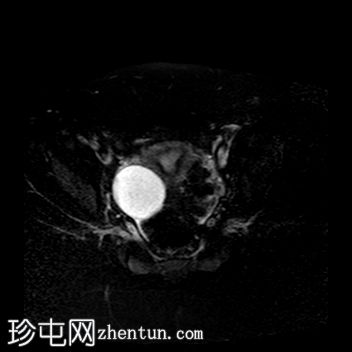

轴位 T1加权像

脂肪抑制序列

阴道明显扩张,T1加权像呈中高信号,T2加权像呈高信号,耻骨联合下方可见一小局灶性隆起。

右侧卵巢可见一圆形、边界清晰的囊肿,最大轴位径为4.2 x 4.3 cm,T1加权像呈低信号,T2加权像呈高信号。